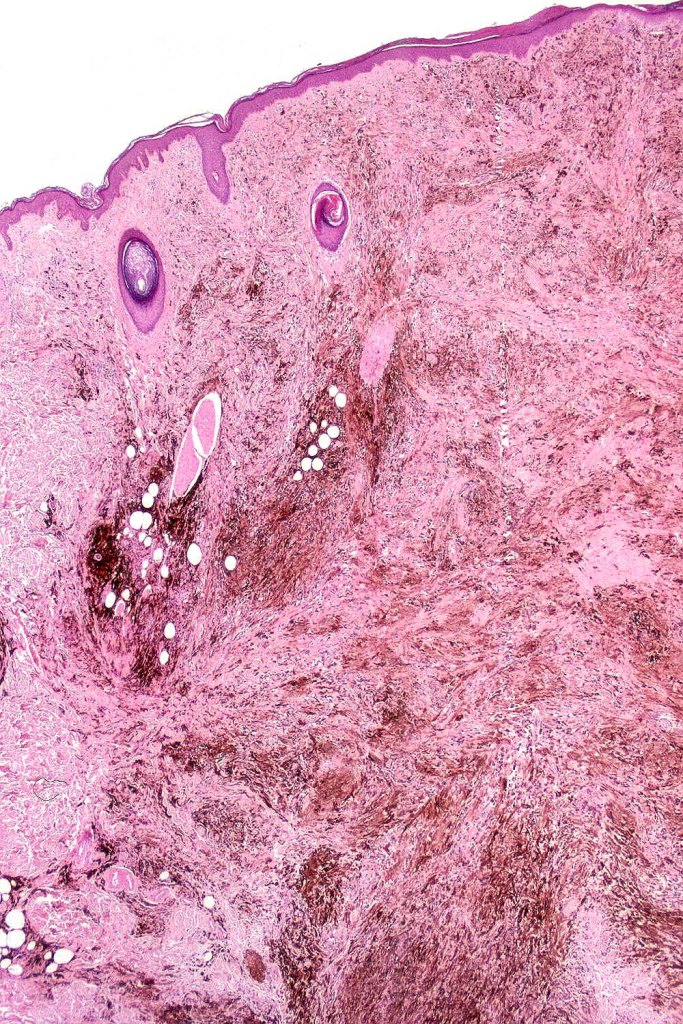

Histological features

•Most characteristic is the dumbbell silhouette although a plague morphology may also be encountered

•An alveolar pattern is characteristic particularly with clear cell nodules

•Stromal fibrosis, myxoid change, vascular hyalinization with cyst formation are often seen